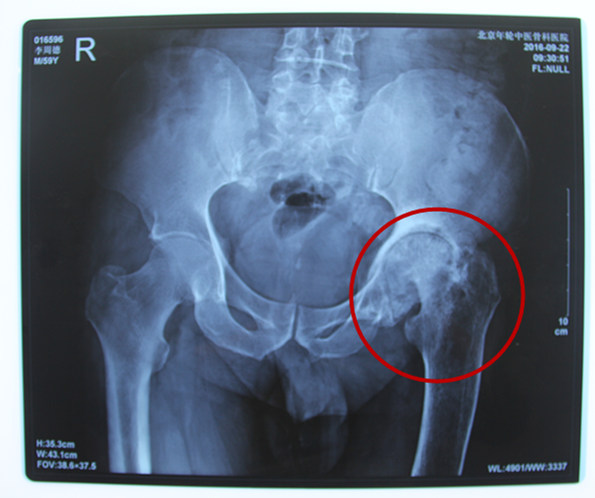

诊断结果:左侧股骨头坏死(Ⅳ期)伴气滞痰淤症、双髋关节骨性关节炎

病情描述:患者于25年前因劳累后左髋关节疼痛且有跛行症状,于当地医院诊断为左侧股骨头坏死,进行自行服药,未加以治疗。2016年因状况剧烈疼痛影响正常生活,选择到医院进行治疗。9月在残联的帮助下加入到了站立计划的项目中来。由于家庭原因,支付能力有限,经特殊批准得到了站立计划的全额救助

2016年9月20日来到北京年轮中医骨科医院接受治疗。经年轮股骨头医师会诊后决定对股骨头坏死病变区进行左髋关节滑膜切除、清理并修正松解;同时取髂骨进行骨移植微创治疗,并辅以特制中医中药调理病况,由康复医师指导日常髋关节功能的恢复。